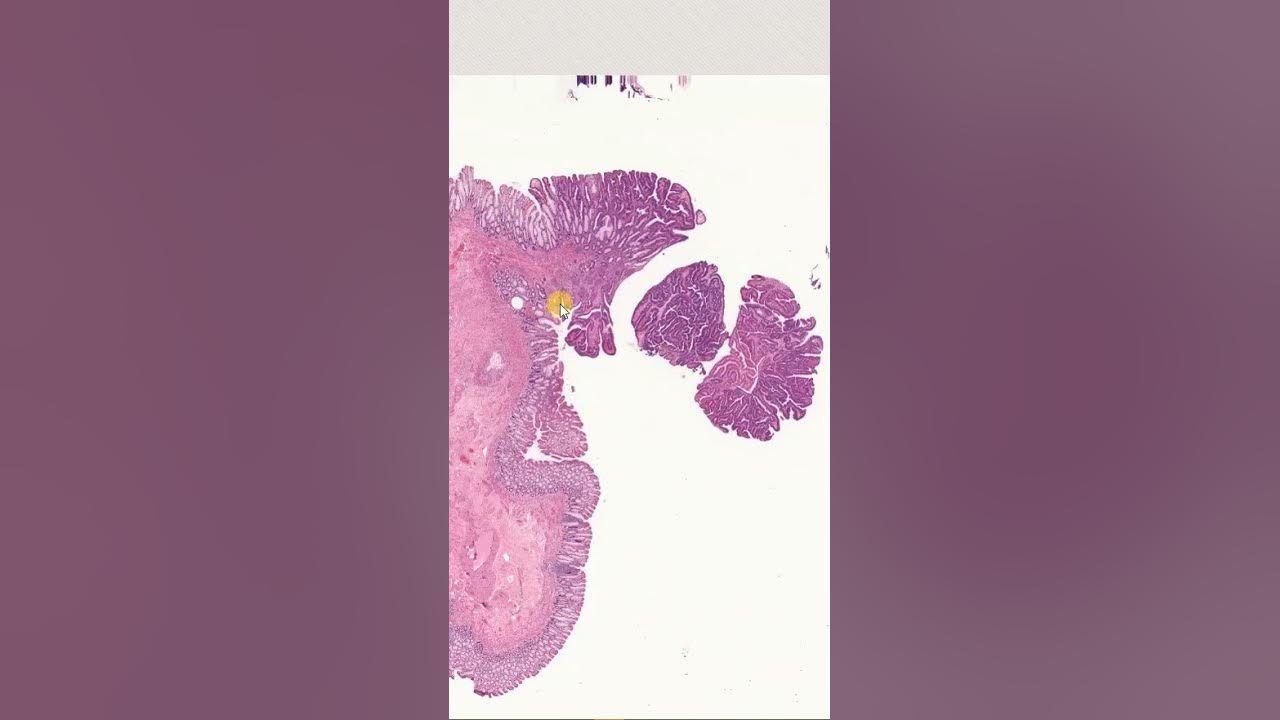

Adénome colique Avec foyers de dysplasie de haut grade shorts pathology Gipath YouTube

Dépistage organisé du cancer colorectal : Guide du format des données et définitions des indicateurs de l'évaluation épidémiologique. La dysplasie est un précurseur du cancer. Il existerait une filiation entre inflammation muqueuse, dysplasie de bas grade, dysplasie de haut grade, et cancer. Définition Ensemble de modifications cytologiques et histologiques épithéliales précédant le développement d'un adénocarcinome caractérisé. C'est une prolifération épithéliale néoplasique indiscutable, mais non invasive.

L'examen histopathologique a confirmé le diagnostic d'adénome villeux... Download Scientific